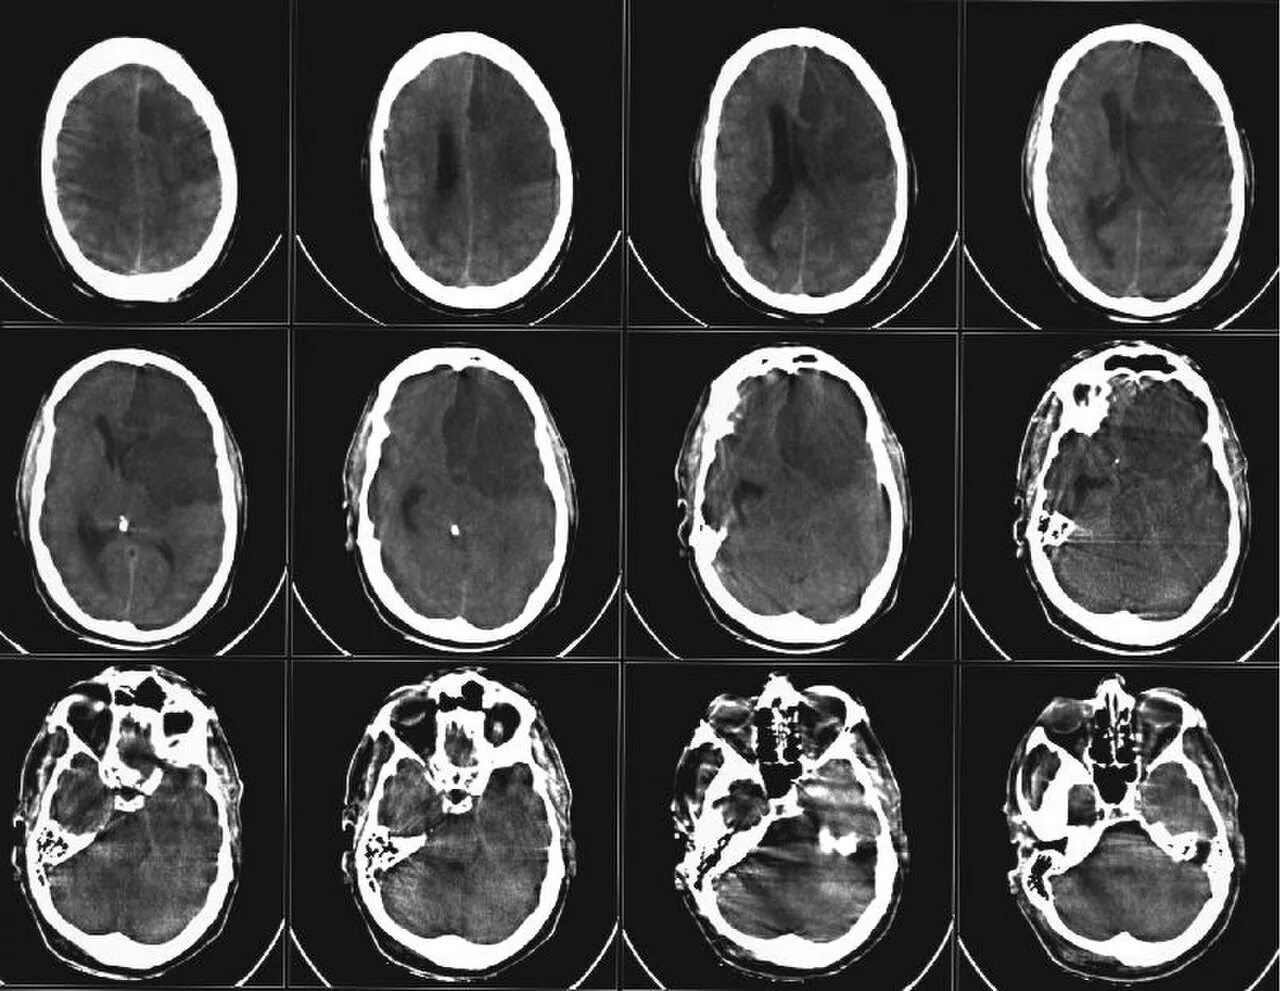

После мрт головного мозга